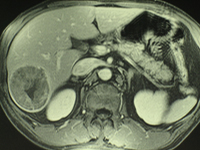

Pseudo kyste du pancréas